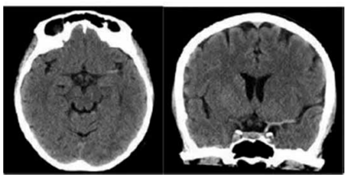

Considere o seguinte caso para responder à questão.

Um paciente do sexo masculino, 63 anos, é trazido ao pronto

-socorro pelos familiares, apresentando afasia e diminuição

da força no membro superior direito, com início dos sintomas

há cerca de 2 horas. Realizou tomografia computadorizada

(TC) de crânio cuja imagem está demonstrada a seguir.

(Arquivo pessoal; imagem usada com autorização)